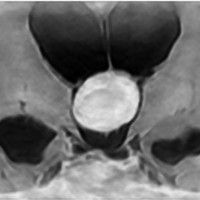

典型的な神経腸嚢胞 neurenteric cyst

左のT2強調画像で等信号,中のT2*で高信号,右はCISS画像です。

T1強調画像では,のう胞周囲の高信号の部分は半固体で,中心部の高信号はドロドロの粘液でした。基本的にガドリニウム増強はされません。まれに薄い膜状に一部が増強されることがあります。

境界明瞭は袋状の腫瘍です。椎骨動脈や脳底動脈を包み込むようにふくらんでいます。